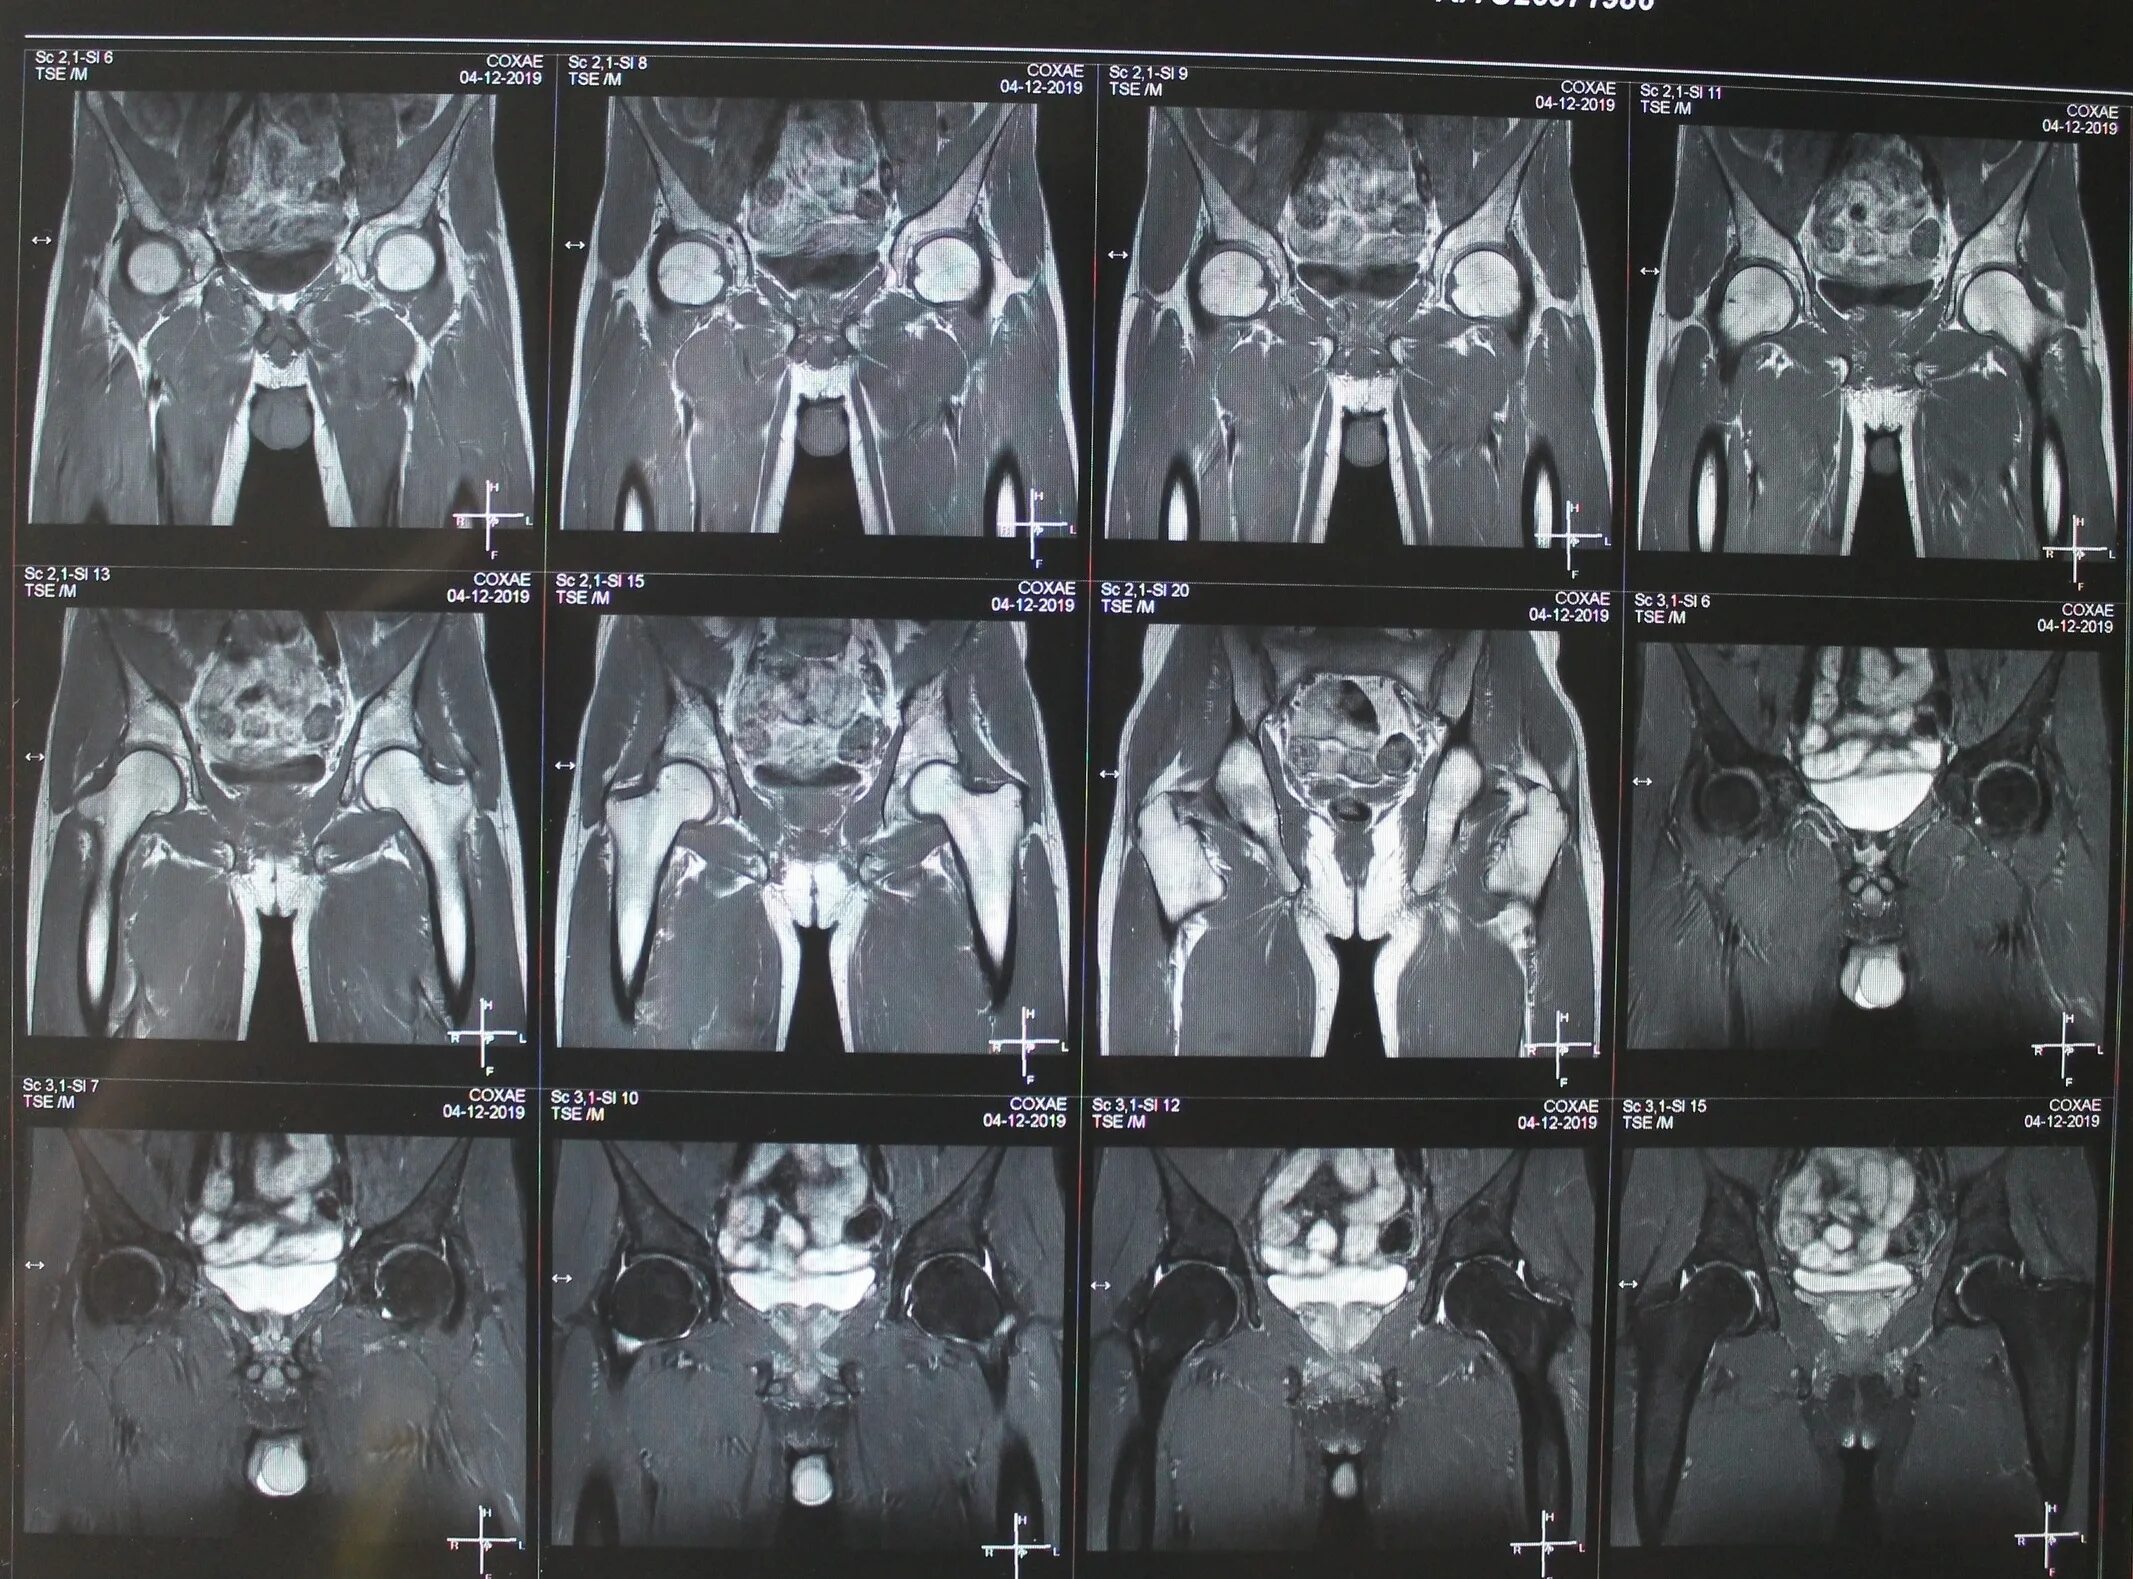

Процедура мрт тазобедренного сустава